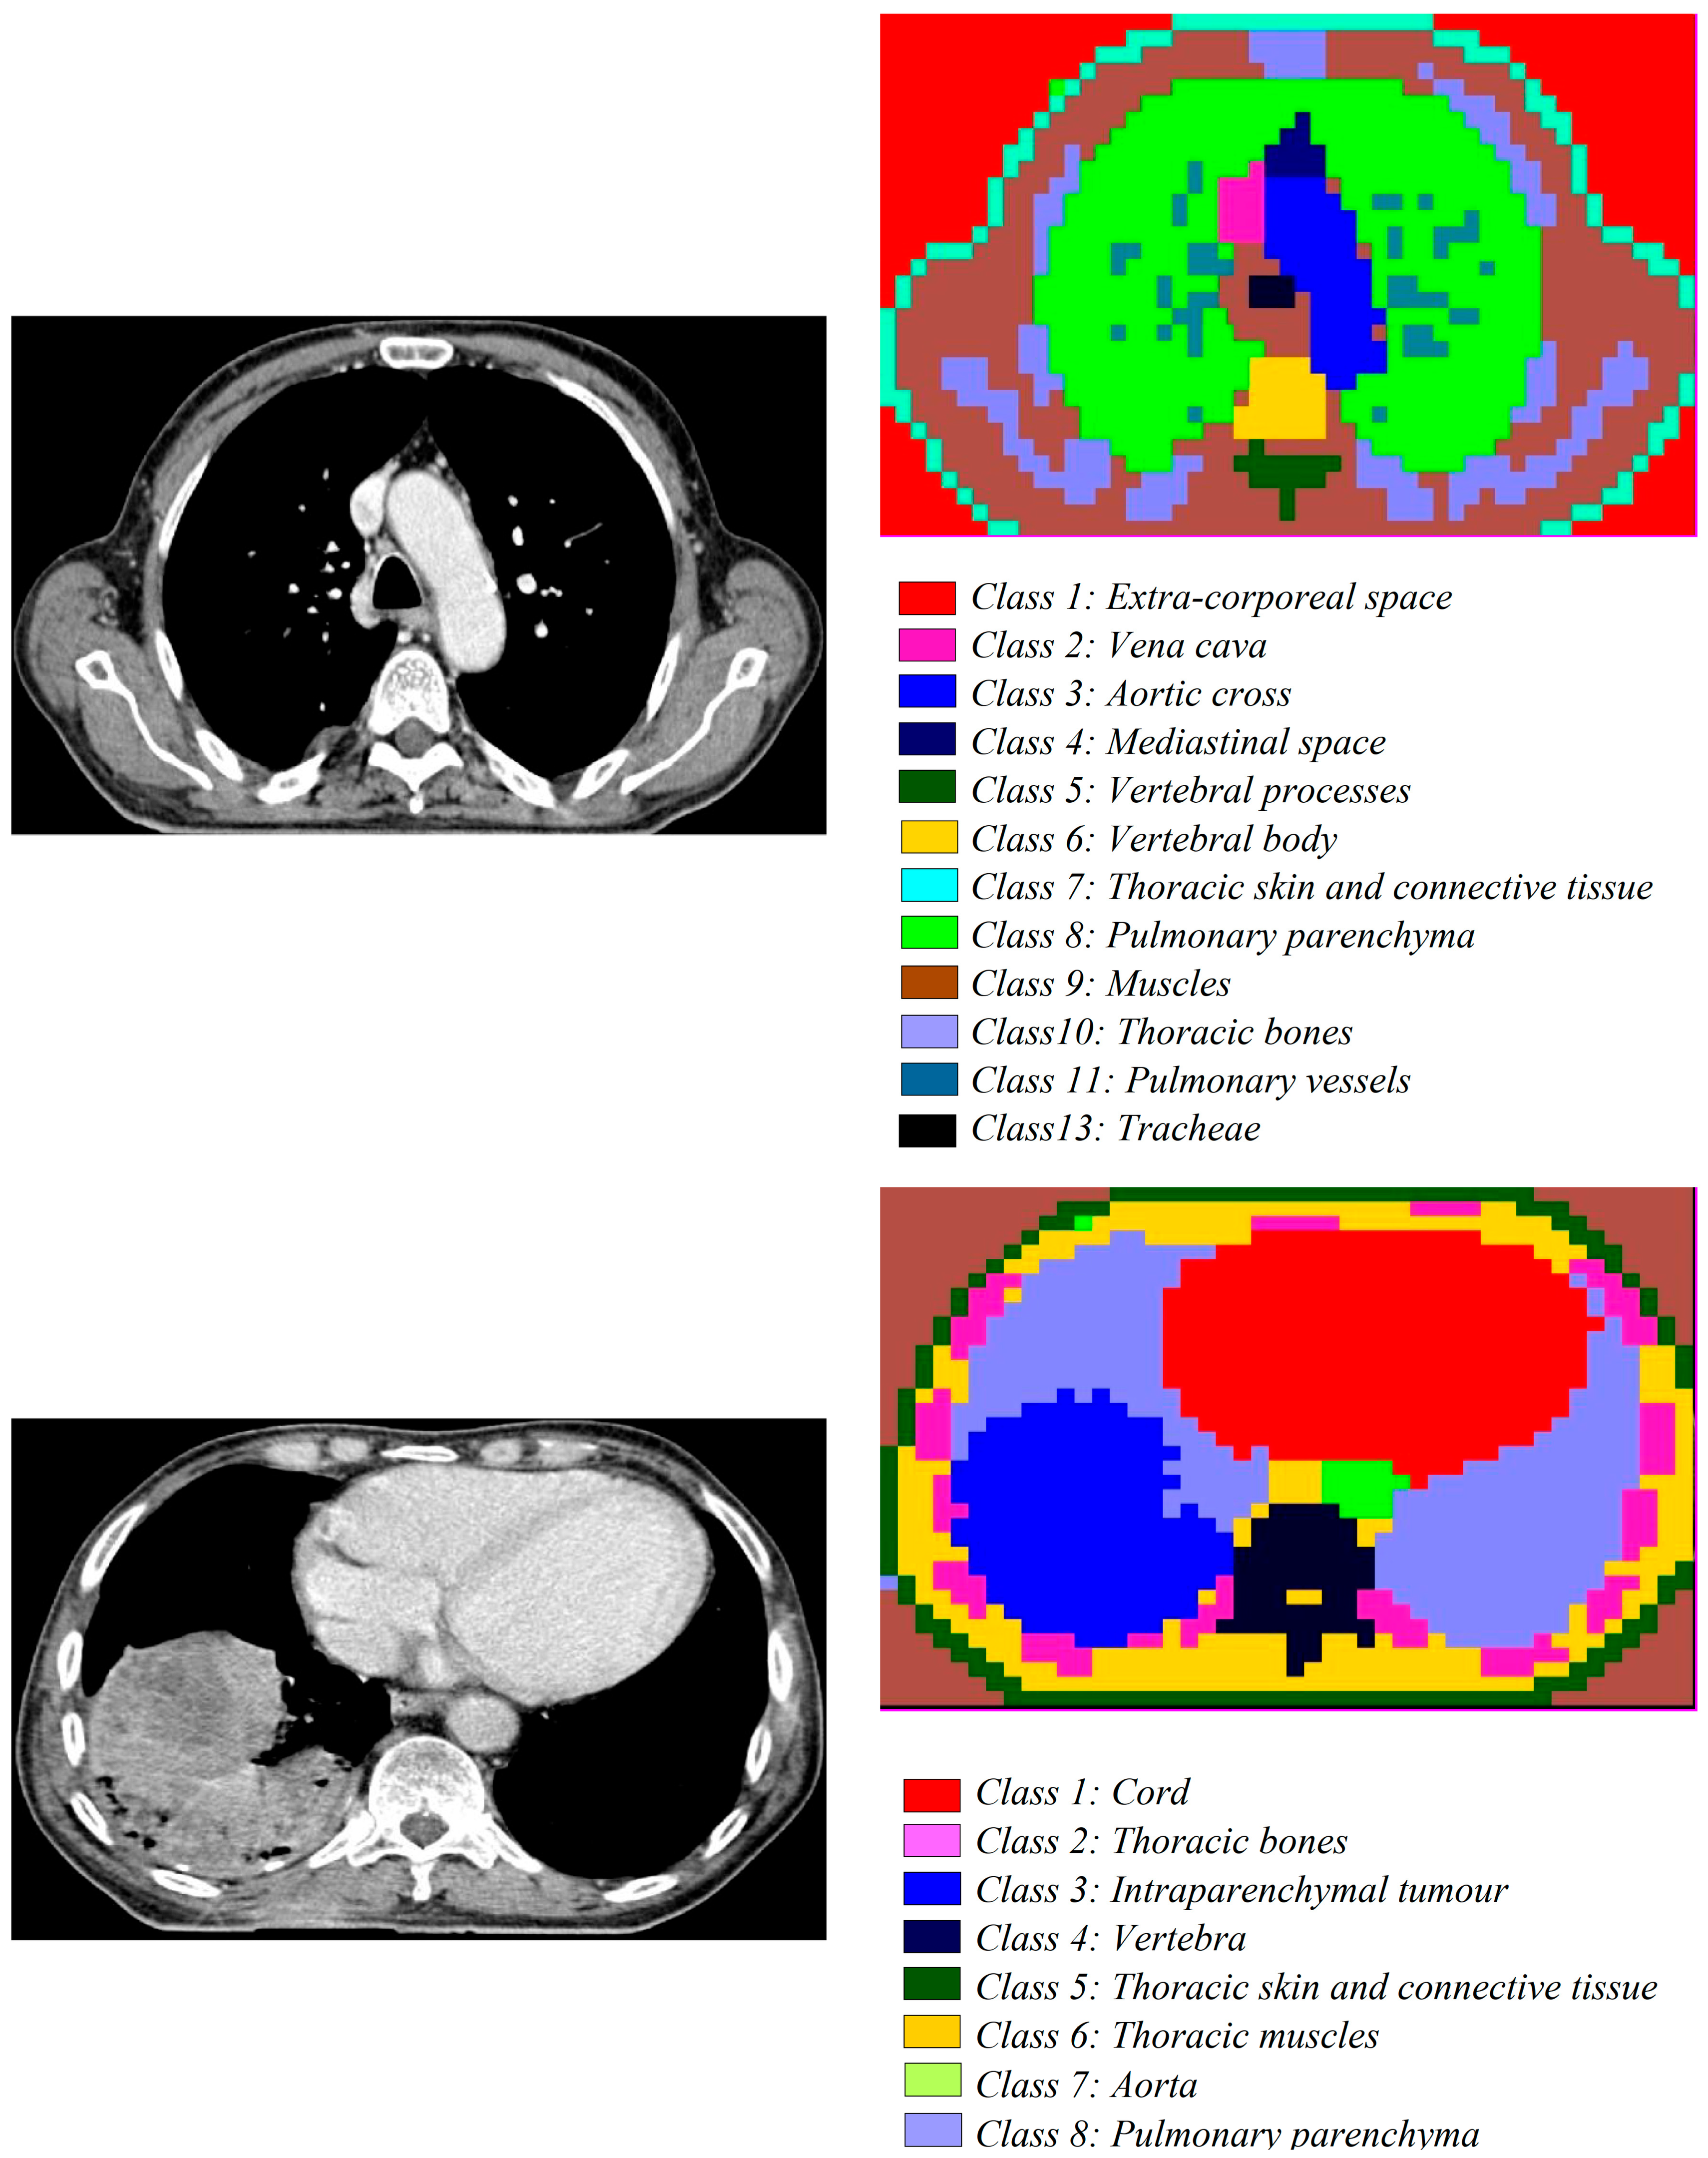

- The second dataset of images is from the patients with lung tumours; there are 11,210 CT images and 25 pathology slices collected from 6 patients. From these, we selected 10 images from 2 patients with lung adenocarcinoma. Usually, lung adenocarcinomas show an admixture of many architectural patterns such as acinar, papillary, micropapillary, lepidic, and solid growth patterns [32,33].

- The third dataset of images is extracted from a collection of 52,072 images from 422 patients with non-small cell lung cancer (NSCLC) [34]. For these patients, pre-treatment CT scans lung tumours; manual delineation by a radiation oncologist of the 3D volume of the gross tumour volume and clinical outcome data are available in [31] for the Lung1 dataset. Typically, lung cancer pathology can identify two groups of cancer cells: small cell lung cancer (SCLC) and non-small cell lung cancer (NSCLC). Then, the last ones, the NSCLC, are divided again into squamous cell cancer (SCC), large cell cancer, and lung adenocarcinoma. Finally, in situ (ISA) and invasive are the two types of lung adenocarcinoma.

3.1.2. Medical Images

| Non-small cell lung cancer | Computer tomography (CT) scan | 1/1 | avg. 1802 × 884 | 1372 × 672 | 4 × 4 | 57,624 |